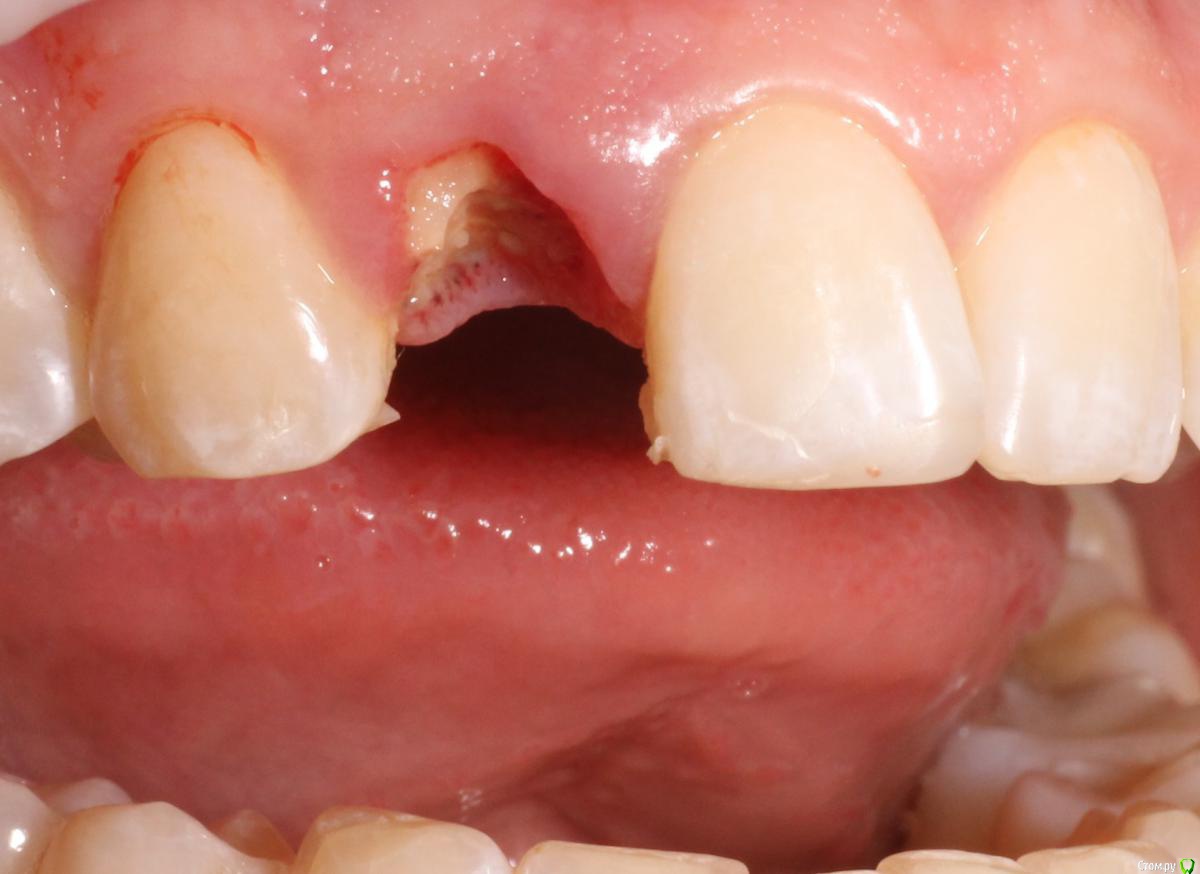

MenshikovDV Опубликовано 2 апреля, 2015 Поделиться Опубликовано 2 апреля, 2015 (изменено) Зуб 1.2 отлом коронковой части зуба, на период ожидания приема у хирурга и ортопеда (2 дня) приклеен к соседям. Вся процедура в одно посещение. Где-то часа два. Я ортопед, хирургия не моя, фото мои Изменено 2 апреля, 2015 пользователем MenshikovDV 19 Ссылка на комментарий

Aquarius Опубликовано 5 апреля, 2015 Поделиться Опубликовано 5 апреля, 2015 в такую дыру лучше что-нибудь кинуть, имхо. Ссылка на комментарий

Alexey Doc Опубликовано 5 апреля, 2015 Поделиться Опубликовано 5 апреля, 2015 Класс! Аккуратно сработали!Единственно, думаю что аугментации была бы желательна. Ссылка на комментарий